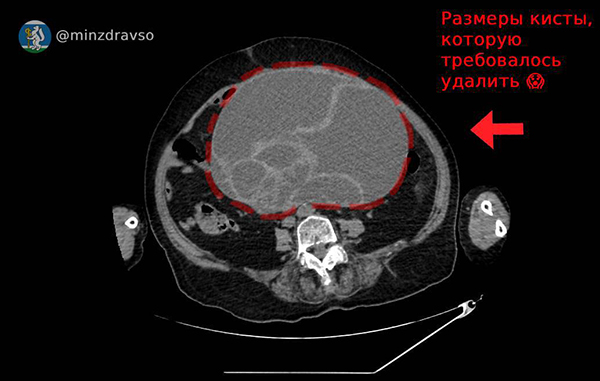

Красноуфимские врачи удалили у пенсионерки кисту в 4,5 килограмма

Врачи Красноуфимской районной больницы спасли 86-летнюю пациентку, удалив из ее тела кисту в 4,5 кг. Об этом сообщает пресс-служба свердловского минздрава.

Гигантская киста была обнаружена в брюшной полости пенсионерки. Ее размер составил 32х25х22 сантиметра, из-за чего все органы внутри были сдавлены. Как рассказал заведующий отделением акушерства и гинекологии Красноуфимской РБ Юрий Шахурин, кисты такого размера встречаются крайне редко.

Размер 4,5-килограммовой кисты, удаленной у пациентки в Красноуфимской районной больнице(2025)|Фото: пресс-служба Минздрава Свердловской области